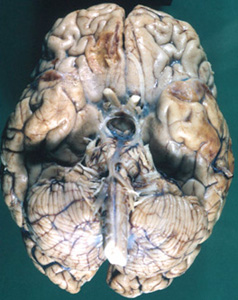

Question 23: The brain lesions in the 57 year old man shown below are most likely due to:

Correct. The most likely cause of bilateral hemorrhagic necrosis of the inferior frontal and temporal lobes is HSV encephalitis. However, contre-coup contusions may have similar distribution. PCA occlusion does not involve the frontal lobes.

Incorrect. The most likely cause of bilateral hemorrhagic necrosis of the inferior frontal and temporal lobes is HSV encephalitis. However, contre-coup contusions may have similar distribution. PCA occlusion does not involve the frontal lobes.